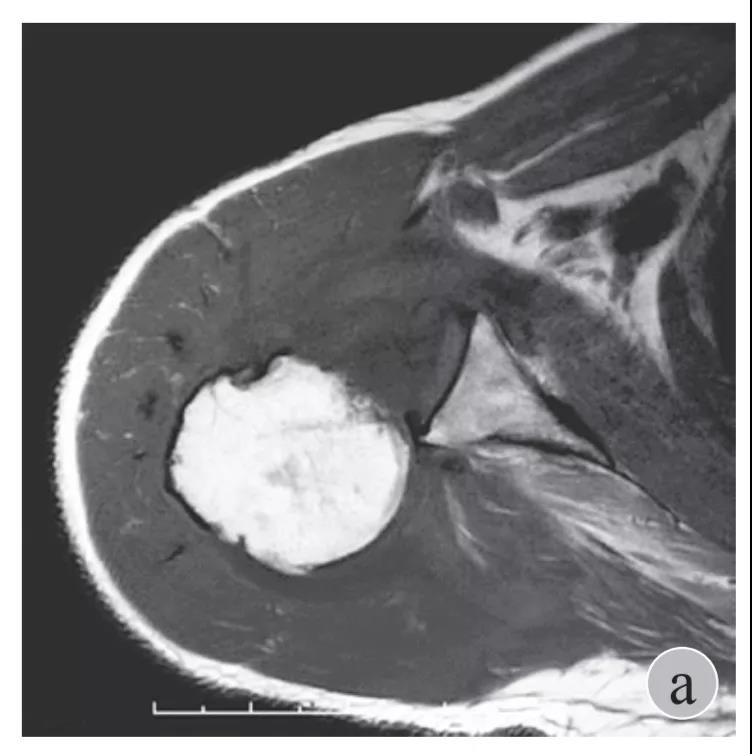

简要病史:骑摩托车跌倒致左肩部肿痛,活动受限,就诊于当地医院,拍片及磁共振检查后诊断为肩袖损伤及肩关节半脱位,予以悬吊固定,因症状缓解不明显就诊于我院。外院拍片情况如下:

磁共振检查也完善了,还是报了个肩关节半脱位……影像科已经把坑挖好了……

就诊我院后完善CT,诊断明确——左肩关节后脱位: